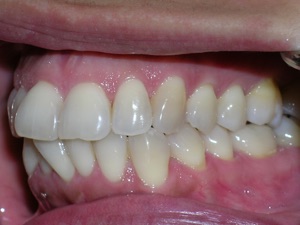

Here’s an example from a woman who had very significant crowding. There was a missing tooth on the bottom right. We considered extracting three other teeth, but decided not to.

Instead we decided to do braces and treat on a non extraction basis with trimming or shaving between teeth to create additional space.

We placed braces and begun a process of trimming or narrowing select teeth. Note that it is a painless procedure, and no anesthesia was needed.

Here are the results.